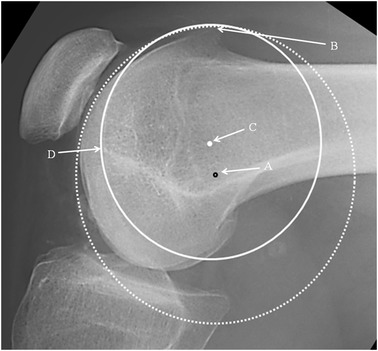

The radiographical analysis began by identifying the femoral tunnel position as defined by Schöttle [17] and marked ‘A’ (Fig. 1). Schöttle’s point lies just distal and anterior to a line drawn at right angles to an extension of the posterior femoral cortical line. The boss height was then measured [14], which is the distance between the extension of the anterior femoral cortical line and the right angle to the most anterior point of the groove. Using the ellipse tool available on the PACS program, and on the assumption that a dysplastic groove is an arc of a circle, a circle was created to match the groove. Circularity was confirmed by measuring and equalising the diameters at right angles. The centre of this circle was defined as the “isometric point” and marked ‘C’. The distance between A and C was measured and recorded. Using the anatomical axis (horizontal offset), the distance proximal (negative) and distal (positive) between A and C, and the right angle to this (vertical offset) were measured. The vertical offset was defined as positive if anterior and negative if posterior to the anatomical axis. No special scaling program was used to correct for any magnification errors and the results were measured in millimetres rounded to the nearest 0.5 mm. Two further measurements were taken, from point A to the most anterior point of the boss (B), and also from point A to the most distal point of the trochlea (D). The PFI cohort was further subdivided into those with a boss height < 5 mm and those whose boss height was ≥ 5 mm. A boss height of ≥ 5 mm has been defined as significant TD [6].

Lateral radiograph of the knee showing: A Schöttle’s point. B Most anterior point of the groove (also the point where the boss height is measured). C Isometric point (centre of the circle that includes the groove). D Most distal point of the groove. Black arrows indicate convention chosen for defining relative position of a point

It was noticeable that when applying a circle to the groove line in the PFI cohort, the circle could be placed to touch two points on the groove, e.g., B and D (Fig. 3) or the circle could match much of the groove (Fig. 4). In the control cohort the groove matched a circle. In Fig. 3, for a patient with TD, it can be seen that the isometric point is anterior to Schöttle’s point, and the radius of the circle from Schöttle’s point to the apex of the boss is longer than that for the best-fit circle. This would result in a significantly anisometric graft if the Schöttle’s point was used as the femoral tunnel position. In Fig. 4, in TD, isometric point moves anteriorly as the circle is made smaller. This implies that there is potential for significant error in the isometric point position in TD. A much more complex methodology is needed requiring 3D reconstruction and analysis of the tracking of the patella to define the femoral tunnel position in the presence of TD. This is not appropriate for the surgeon in a clinic. Interestingly, using 3D CT scans in different degrees of knee flexion, Blatter et al. [4] only found one isometric point in 10 normal knees when measuring the MPFL length with a maximal length difference during knee flexion of 10 mm. They also noted that for most, the optimal tunnel position was slightly anterior to Schöttle’s point. It would be interesting to know how this correlated with the lateral plain radiograph.

Lateral radiograph of the knee showing: Schöttle’s point: black rimmed spot (A). Isometric point: white spot (C). Dotted circle: centred on Schöttle’s point with the radius to the highest point of the boss (B). Complete circle: centred on the isometric point. Note that the dysplastic groove is not an arc of this circle. Point D is the distal end of the notch